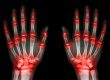

Cuando se trata de lesiones ortopédicas, la atención temprana puede marcar la diferencia entre una recuperación rápida y efectiva o un proceso prolongado y complicado. En Cecoten, comprendemos la importancia de abordar de manera oportuna y adecuada las lesiones musculoesqueléticas. A continuación, exploraremos la relevancia de la atención temprana en el tratamiento de lesiones ortopédicas y cómo nuestros especialistas en Cecoten están capacitados para brindarte la atención necesaria para una recuperación exitosa.

Al abordar una lesión ortopédica de manera temprana, podemos prevenir la aparición de complicaciones y secuelas a largo plazo. El tratamiento oportuno puede ayudar a reducir el dolor, la inflamación y la posibilidad de daño adicional en los tejidos afectados. Además, nos enfocamos en restaurar la funcionalidad y movilidad de la zona lesionada, evitando limitaciones a largo plazo y promoviendo una recuperación completa.